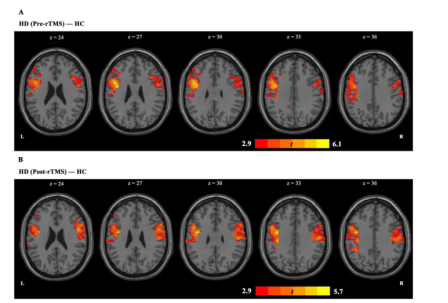

In 2022,The team of Longxiao Wei of Tangdu Hospital of the Air Force Military Medical University uses the transcranial magnetic stimulation (TMS) device for sale (M-100 Ultimate, YINGCHI, Shen Zhen, China) to analyze the functional connections between the default mode network (DMN) and other brain networks of 30 heroin addicts before and after 7 times of transcranial magnetic stimulation. Studies have shown that repetitive transcranial magnetic stimulation can regulate the functional connection between the default functional network and the executive control network, and the change of functional connection between the left inferior parietal lobule and the left middle frontal gyrus may play an important role in reducing drug cue-induced craving.[12]

FMRI